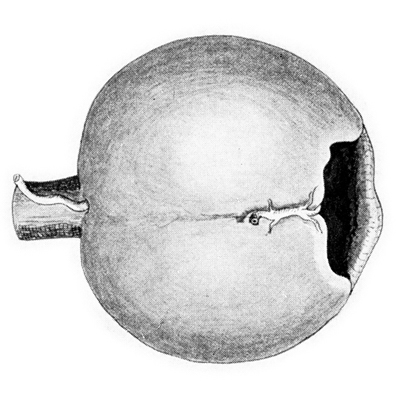

Aniridia

Es un término empleado al examen clínico, porque en todos los casos existen algunos rudimentos presentes al examen anatómico y microscópico; se asocia a mala visión, nistagmus y ausencia del reflejo foveal. (5,8)

Existen muchas teorías sobre el momento en que ocurre el error y de que tejido depende, siendo la más aceptada la teoría Ectodérmica, que postula una detención germinal de la diferenciación en la copa óptica en la etapa de los 70mm, cuando ya las capas de la retina se han diferenciado, todavía no hay fóvea, el íris ectodérmico esta presente como un estrecho reborde debajo de la unión corneoescleral, y la mayoría de los vasos cápsulo-pupilares han desaparecido. Lo que no queda claro es la razón para la ausencia casi total del iris mesodérmico, que se forma alrededor de los 48 mm. Las tendencias de la teratología hacen énfasis en la importancia de las estructuras ectodérmicas en la iniciación y control del crecimiento.

Aniridia completa, catarata y distrofia corneal de la aniridia

Archivo Dr. Francisco Barraquer

Caso de paciente con Coloboma en un ojo y Aniridia en el contralateral

OD

Archivo Fotográfico Dr. Francisco Barraquer

OI

Archivo Dr. Francisco Barraquer

Existen también las teorías Mesodérmicas, una de las más discutidas, es la que soporta que la falla ectodérmica es producida por persistencia indebida del mesodermo embrionario, especialmente aquel de la porción cápsulo-pupilar de la túnica vasculosa lentis. Es cierto, que en los casos típicos y atípicos de coloboma del Iris, hay evidencia clínica y patológica de persistencia indebida de uno o mas vasos cápsulo-pupilares (iridohialoideos); si se considera la Anirídia como un Coloboma Total del Iris, entonces la causa que induce la detención del desarrollo del Iris en los colobomas actuando simultáneamente en todo el círculo, causaría la Anirídia.